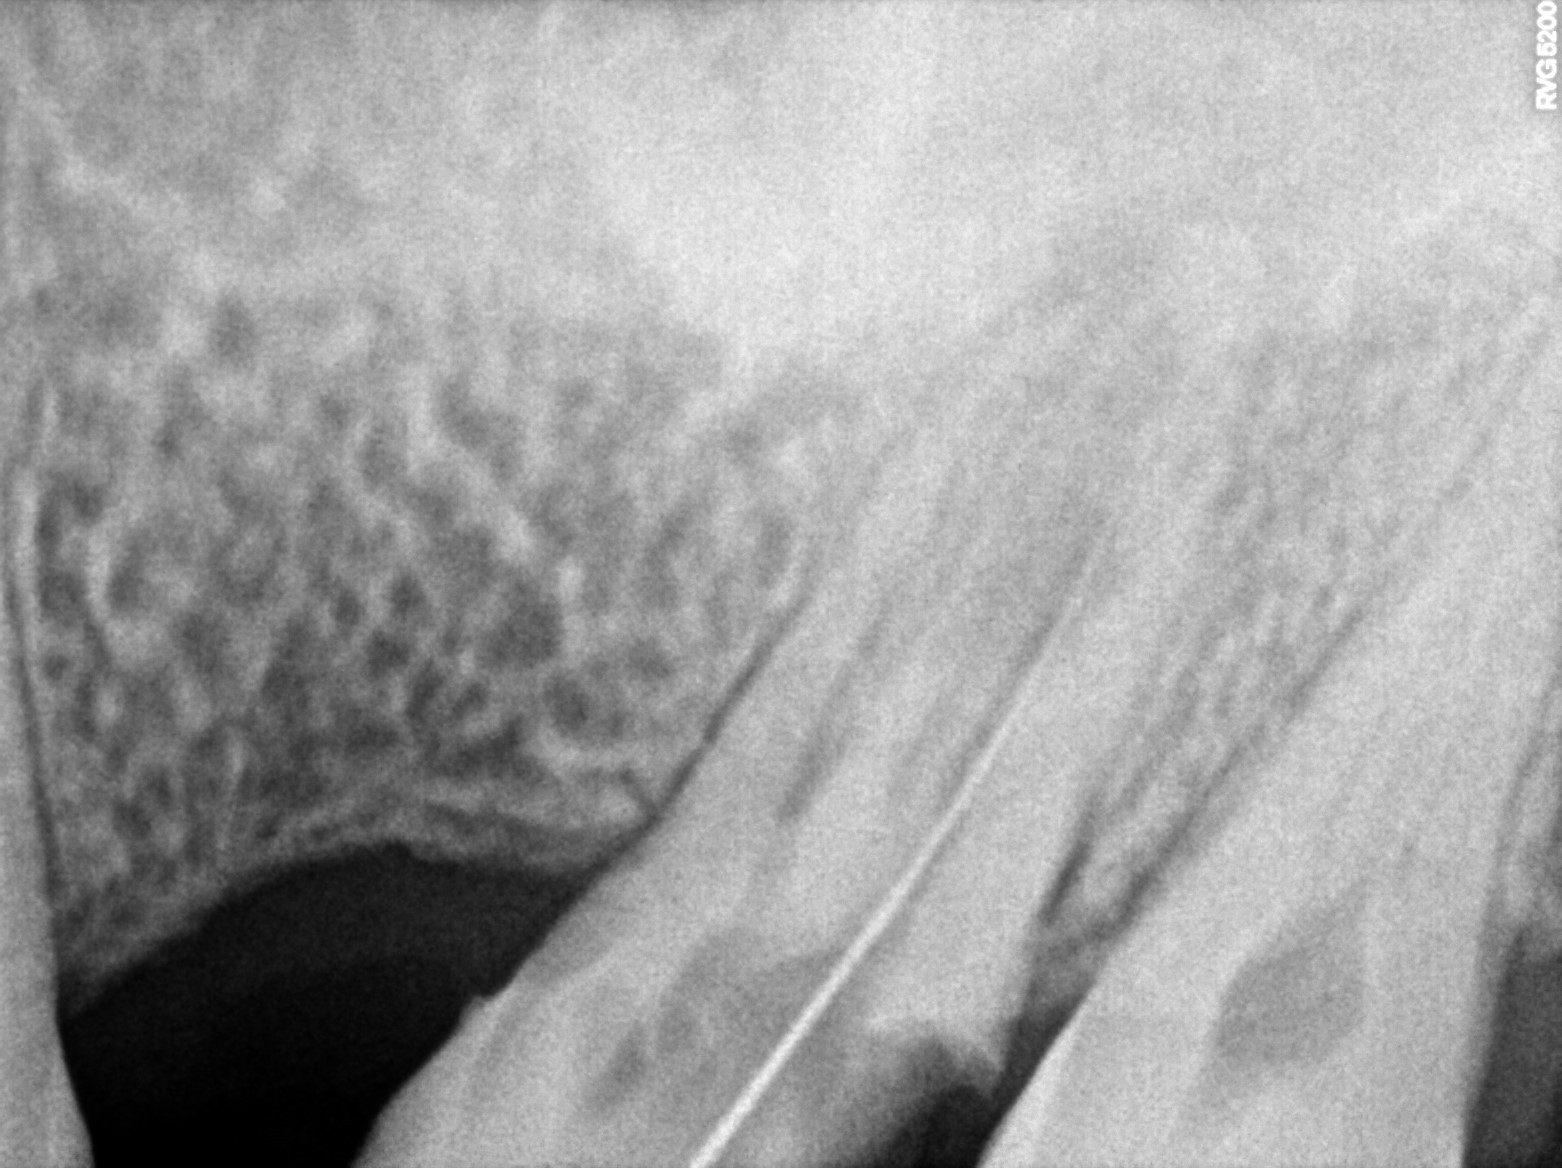

Dental Radiographs FHIR: DocumentReference · LOINC 24641-7

xray_1773248555_0.jpg

24641-7